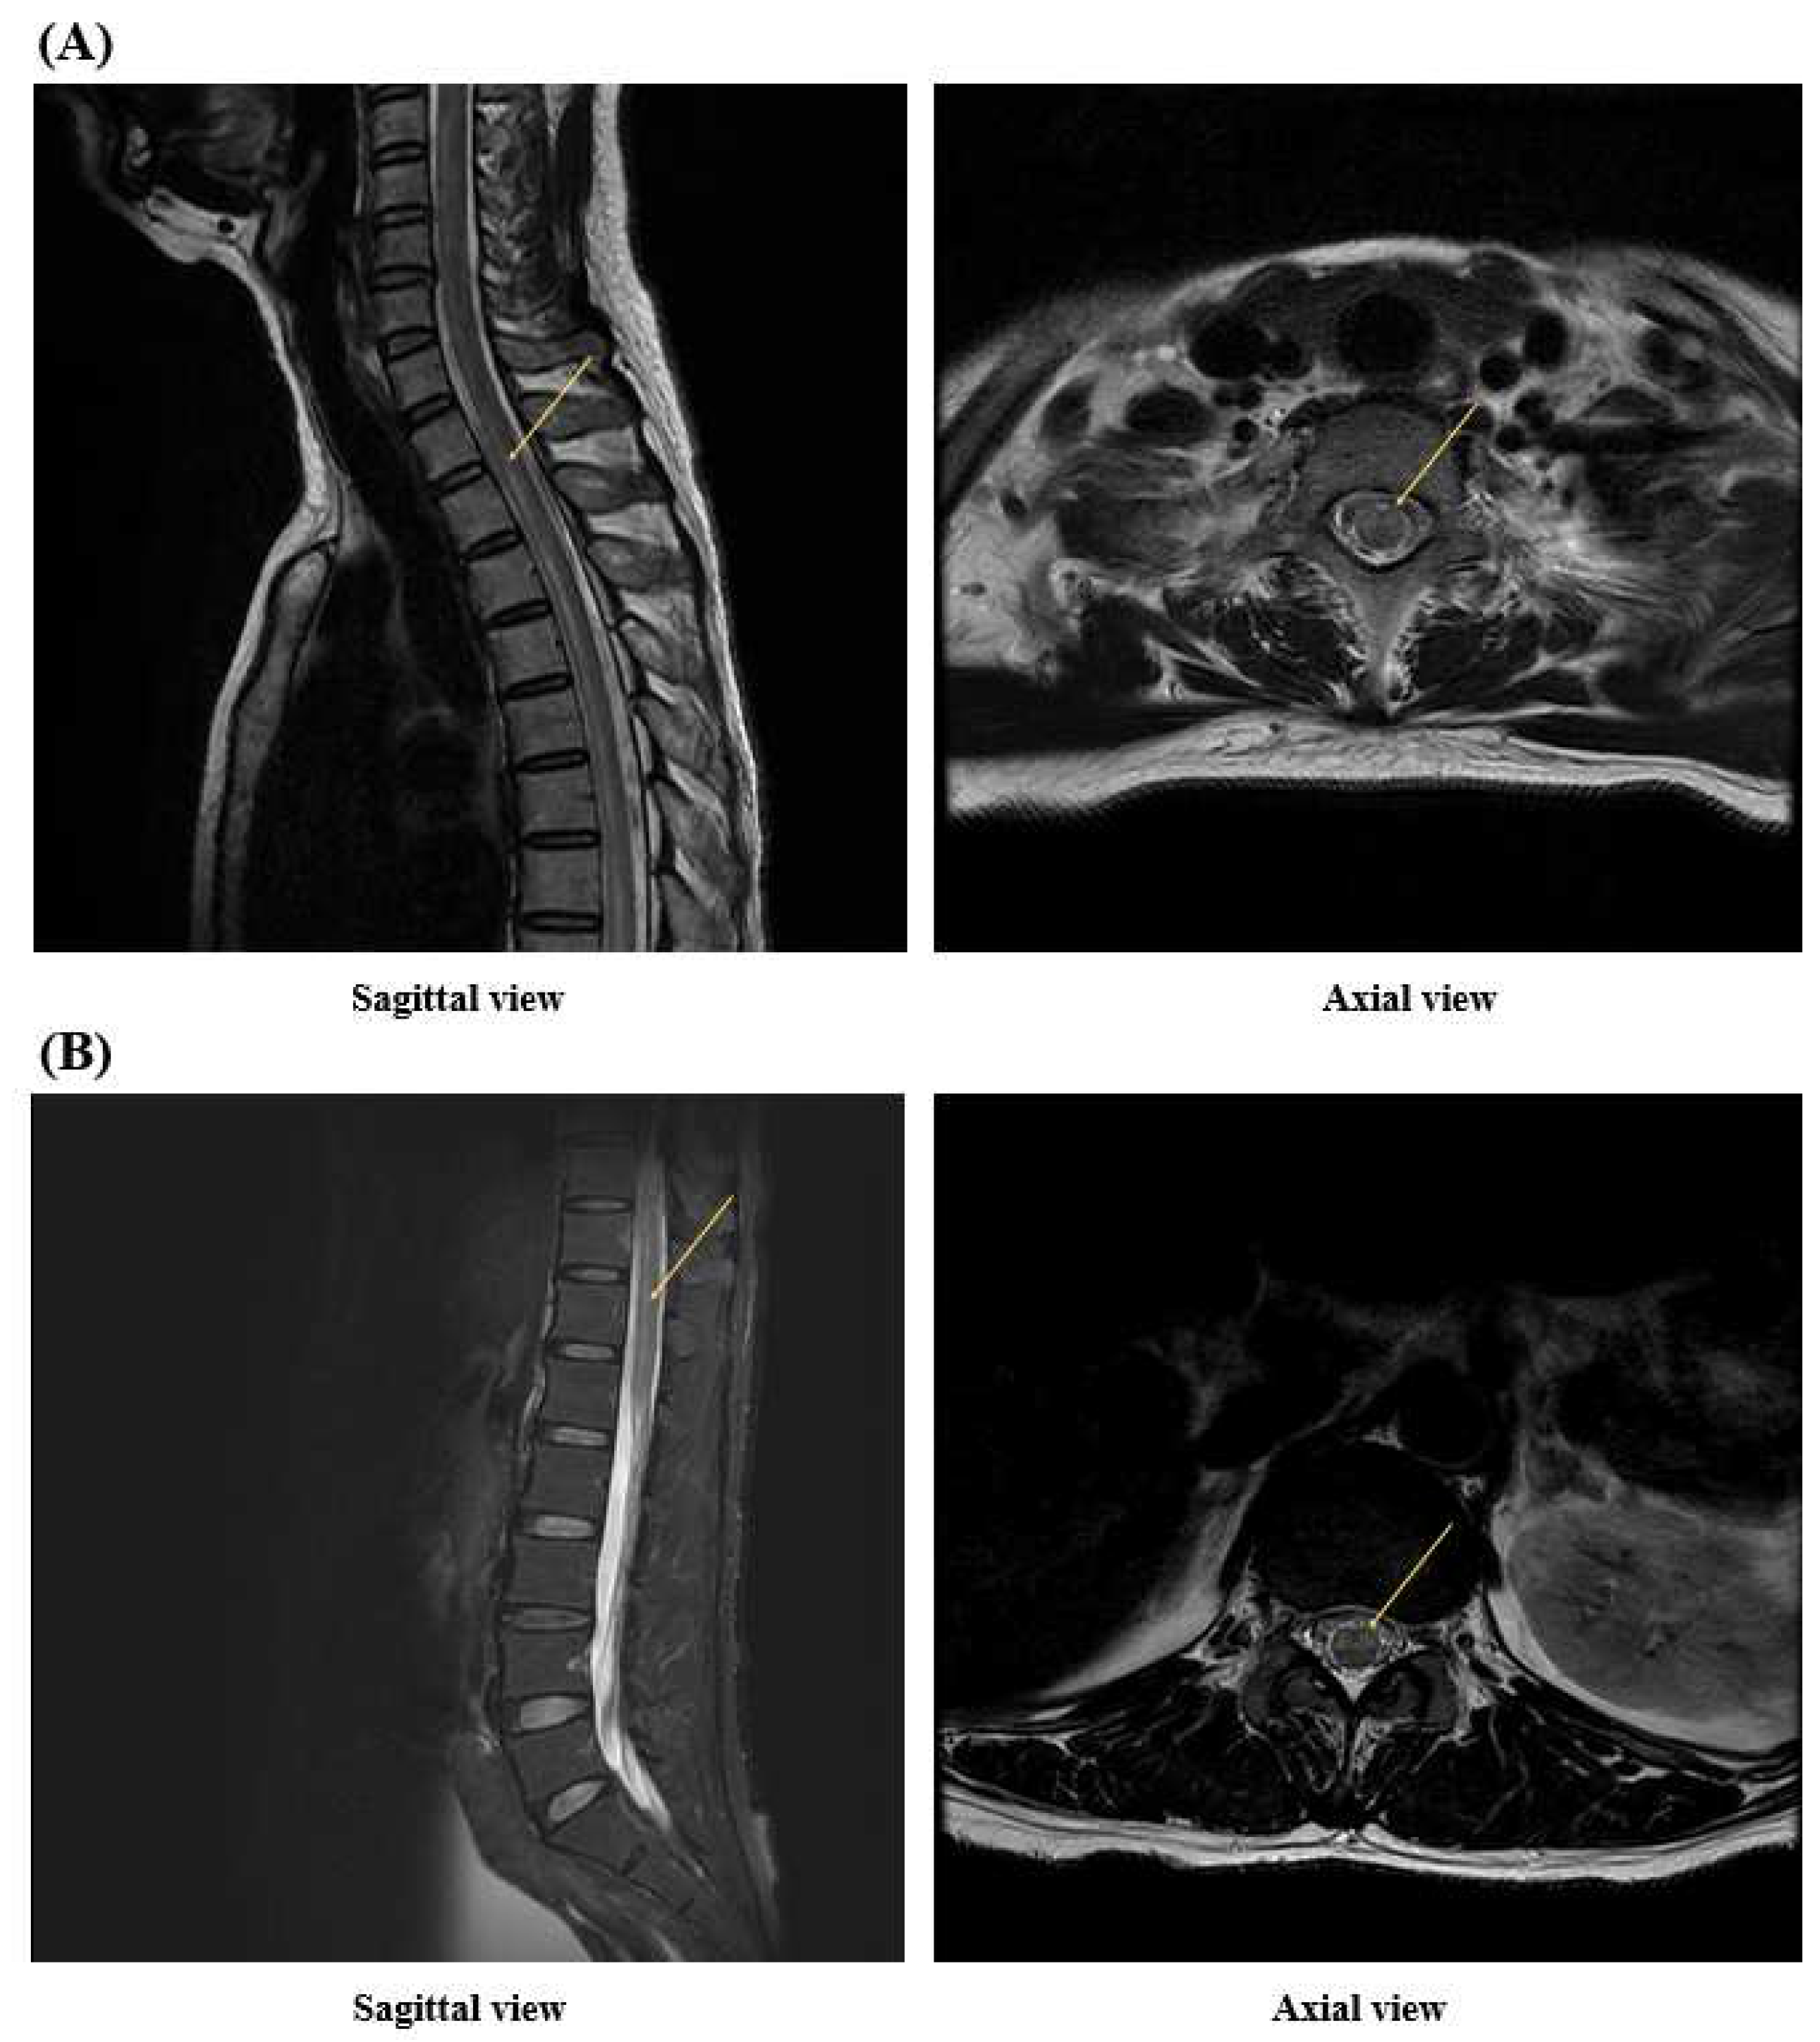

2. Case Presentation